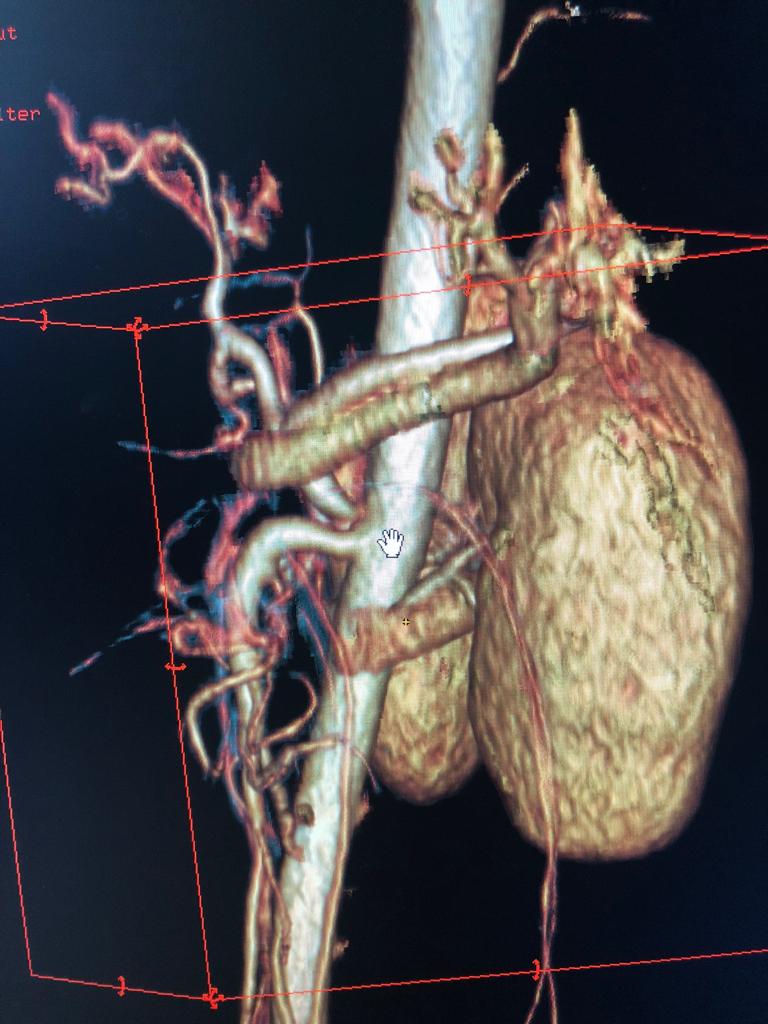

A Challenging Scenario: 40-year-old male with idiopathic chronic pancreatitis with intractable pain and sitophobia

40 year old male with idiopathic chronic pancreatitis presented with intractable pain, sitophobia with severe weight loss (adult male weighs 29 Kg) and history of recurrent episodes of GI bleed. He also has CKD (cr1.7) related to neurogenic bladder. Patient was shifted to us in shock with HB 3 gm % and massive GI bleed. MRI and CT angio showed a large 6x5 cm Pseudoaneurysm in uncinate process of pancreas probably arising from inferior pancreaticoduordenal artery causing hemosuccus pancreas. In view of CKD we chose to tackle aneurysm by direct glue embolisation of aneurysm sac to avoid the high volume contrast of conventional angio (image) Pt was put on NJ feeds in view of severe malnutrition secondary to intractable pain and sitophobia. Post embolisation 2 months later he came back with weight gain of 8 kg and a stable Hb%. His Repeated CT scan showed a persistent intrapancreatic head cyst with dilated pd in body and tail. The aneurysm cavity filled with glue cast has shrunk to almost one fifth the initial size. In view of large duct disease with Pseudoaneurysm we decided to go ahead with a whipple pancreaticoduodenectomy. The post op specimen shows the intrapancreatic cyst and the glue cast of the aneurysm (yellow arrow). His recovery was uneventful and is completely pain free post procedure.